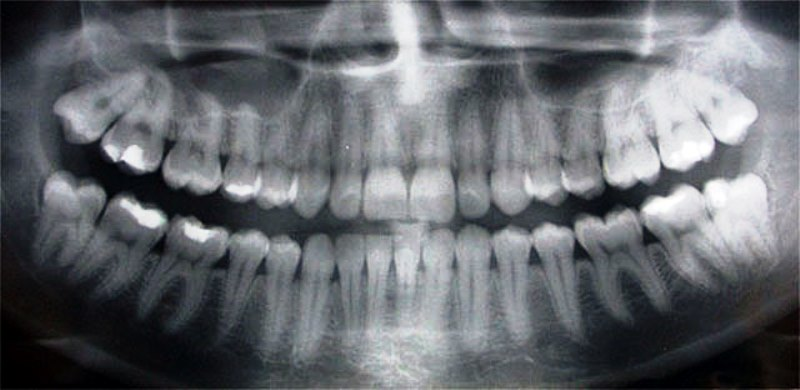

De panoramische röntgenfoto, of Panorex zoals het eerst werd genoemd, is een prachtige moderne uitvinding. Het heeft veel minder straling dan een traditionele volledige set van achttien (18) kleinere röntgenfoto’s en het is voor de patiënt veel comfortabeler om deze te maken. De panoramische röntgenfoto kan ook zeer snel worden gemaakt en is vooral nuttig als een patiënt pijn heeft. Normaal gesproken moet er elke drie (3) jaar een panoramische röntgenfoto worden gemaakt. Het maken van een reeks hiervan bij dezelfde patiënt kan helpen. de tandarts om later te bepalen of de veranderingen op de panoramische röntgenfoto normaal zijn of niet.

De panoramische röntgenfoto is niet hetzelfde als een volledige reeks tandheelkundige röntgenfoto’s. De panoramische röntgenfoto laat veel meer van de patiënt zien dan een heleboel kleinere röntgenfoto’s. Heel vaak is de zenuw die naar de onderlip gaat, de mandibulaire zenuw, niet zichtbaar bij een volledige mondset. Het verlammen van de manibulaire zenuw is een mogelijke complicatie van een tandheelkundige implantaatoperatie. Daarom is het erg belangrijk om een panorex-röntgenfoto te maken wanneer een tandheelkundige implantaatoperatie gepland is.